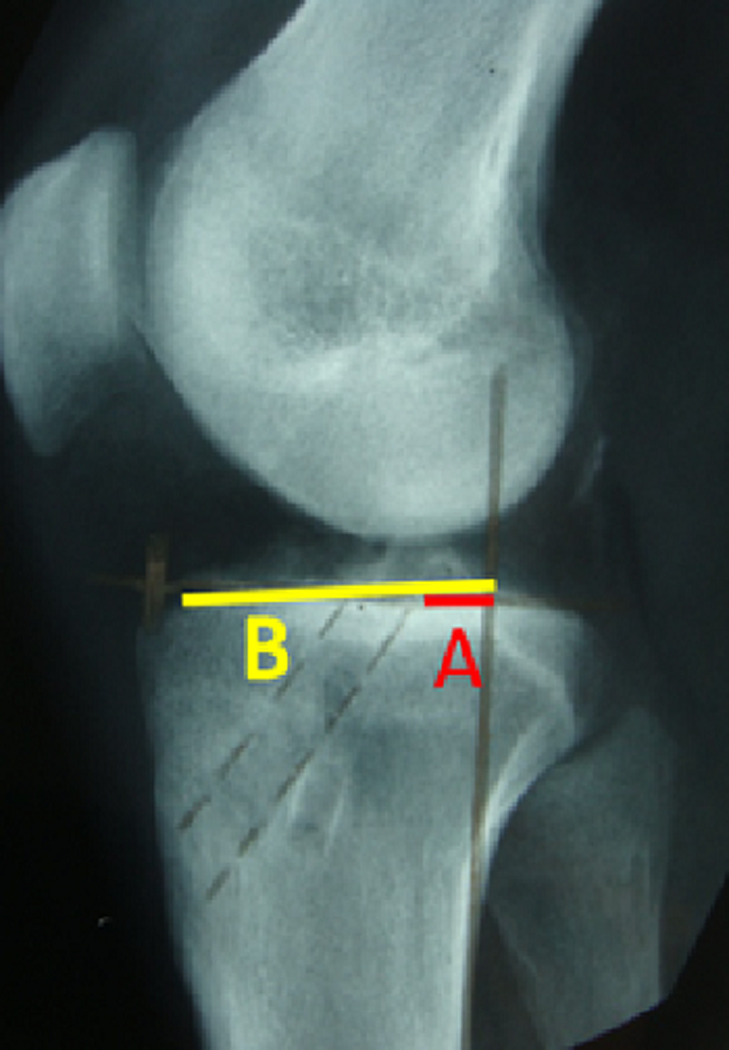

最近关于前交叉韧带(ACL)手术的研究集中在更好地控制旋转稳定性上,但ACL重建一直是一个热门问题。本研究的目的是根据J.H Jaeger改良的Macintosh技术,评估使用带阔筋膜的前交叉韧带解剖重建技术后的临床和放射学结果。我们在2005年至2019年期间对80名患者进行了连续研究。所有患者均根据国际膝关节文献委员会(IKDC)评分和Lysholm和Tegner量表进行评估。我们所有的病人都被评为优秀,平均得分92分。8例患者偶有外侧残留疼痛。残余抽搐占2.5%。在最后一次随访时,放射检查未显示球囊或关节病。前交叉韧带重建是一种常见的手术,随着时间的推移变得更加可靠。但枢轴移位(Jerk test)需要外侧肌腱固定“外旋”,尤其是运动员。

Recent studies about anterior cruciate ligament (ACL) surgery have focused on a better control of rotational stability, but ACL reconstruction is always a topical issue. The purpose of our study was to evaluate clinical and radiological outcomes after the use of the technique for anatomical reconstruction of the ACL with fascia lata, according to Macintosh technique modified by J.H Jaeger. We conducted a study of a continuous series of 80 patients between 2005 and 2019. All patients were assessed according to the International Knee Documentation Committee (IKDC) score and the Lysholm and Tegner scale. All our patients were rated as excellent with an average score of 92. Occasional lateral residual pain was reported by 8 patients. Residual jerk accounted for 2.5%. Radiological examination did not show ballooning or arthrosis at the last follow-up. Anterior cruciate ligament reconstruction is a common procedure that has become more reliable over time. But pivot shift (Jerk test) requires a lateral tenodesis "external rotation", especially in athletes.